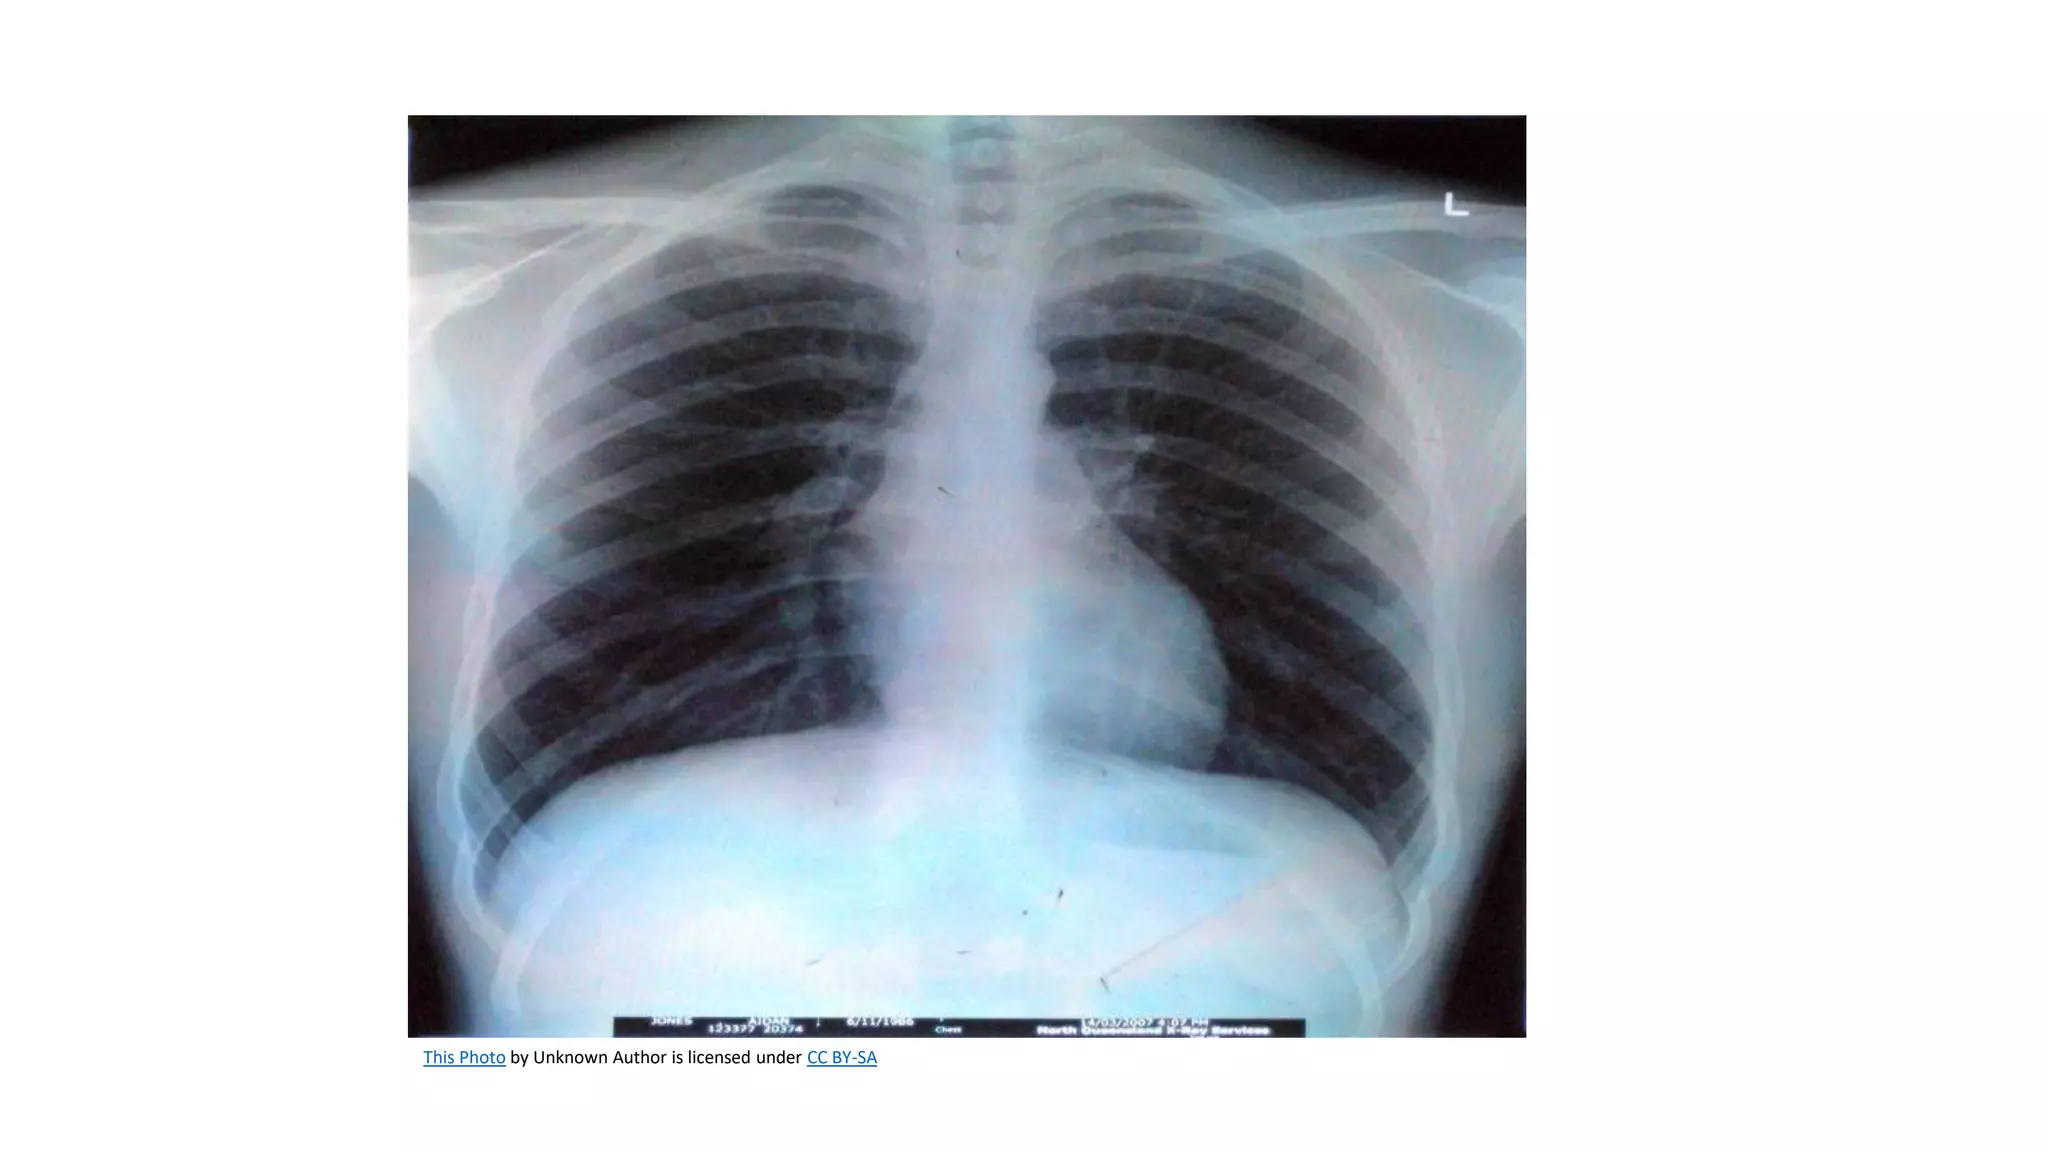

A chest x-ray is obtained to determine the size, contour, and

position of the heart.

It reveals cardiac and pericardial calcifications and demonstrates

physiologic alterations in the pulmonary circulation.

Although it does not help diagnose acute MI, it can help diagnose

some complications (eg, HF).

Correct placement of pacemakers and pulmonary artery

catheters is also confirmed by chest x-ray.

A chest x-rayis obtained to determine the size, contour, and position of the heart. It reveals cardiac and pericardial calcifications and demonstrates physiologic alterations in the pulmonary circulation. Although it does not help diagnose acute MI, it can help diagnose some complications (eg, HF). Correct placement of pacemakers and pulmonary artery catheters is also confirmed by chest x-ray.